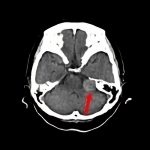

断層撮影

手術前2